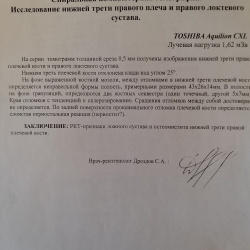

Здравствуйте, подскажите как правильно описать и заключится впервые смотрю локтевой сустава, женщина 55лет, перелом в начале января, жалобы на то что сустав полностью не разгибается. Здесь...